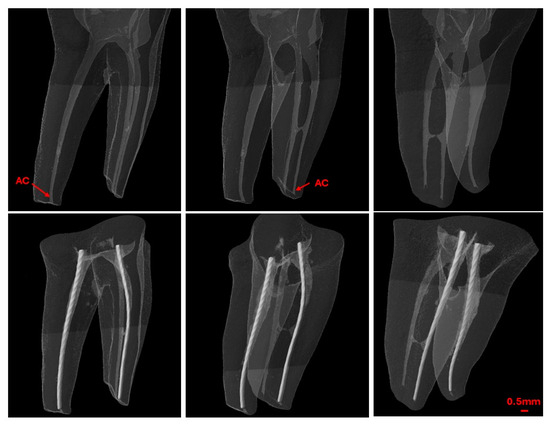

2.6. Second Scan—Post-WL Measurement

After establishing the WL using EAL, a second scan was conducted with the endodontic file fixed within the canal (Figure 4). The pre- and post-scan datasets were co-registered, and the distance between the tip of the endodontic file and the previously identified AC was calculated and recorded as positive or negative values relative to the AC.

For clarity and accuracy assessment, the recorded measurements falling within 0.1–0.5 mm from the AC were categorized as ‘close’. Measurements extending beyond the tolerance level towards the major foramen were categorized as ‘beyond’, otherwise they were classified as ‘far’.

Figure 4. Pre- and post-working length measurement micro-CT scans.